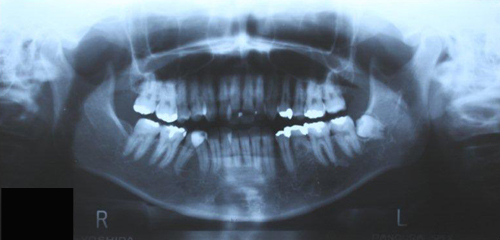

奥歯を噛みしめる癖がある、歯ぎしりで歯がすり減っている、顎が痛い、顎が開きにくい、首や肩がこる、などの症状を改善、予防するための治療をおこなっております。

就寝中の歯軋りや食いしばりは、精神的なストレスや咬み合わせ異常などの口腔環境のストレスから起こりますが、歯や顎に加わる力は食事の時の2倍にもなる大きな負担です。

スプリント療法は就寝中にマウスピースを装着することで、顎関節の変化を起こして歯軋りや食いしばりを改善したり、歯軋りや食いしばりの負担を分散・軽減することで顎関節症の症状を軽減する治療です。

マウスピースは顎関節症の症状や改善目的に合わせて必要な時にその都度製作します。